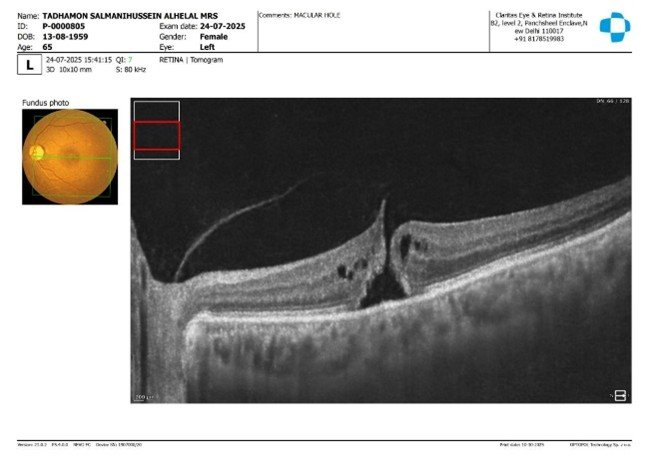

OCT (Optical Coherence Tomography):

To assess the macula's health and identify any retinal damage.

These tests confirmed the presence of a macular hole and a cataract in the left eye, requiring surgical intervention to restore her vision.